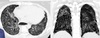

Mulher, 45 anos, dispneia e tosse seca há 5 dias. Passado de transplante pulmonar bilateral.

Bronquiolite obliterante (Bronquiectasias e espessamento das paredes brônquicas + Aprisionamento aéreo + Opacidades em vidro fosco -> Atenuação em mosaico)